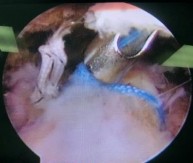

- Sau khi buộc xong các nút chỉ tất cả vùng được bộc lộ ở phía ngoài của nút chỉ và gân CX được tạo thêm một số lỗ vi tổn thương.

Hình 2.27. Tạo vi tổn thương sau khi buộc chỉ khâu CX

* Nguồn: ảnh chụp trong mổ của BN Lê Cao S, số bệnh án 1911250706